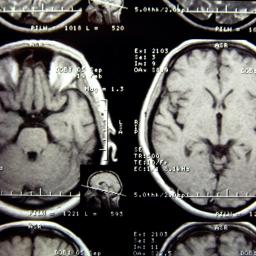

Long Covid: Protein-Ablagerungen im Gehirn wie bei Alzheimer oder Parkinson

Forschende haben in Tieren mit Long Covid-Symptomen ähnliche Veränderungen gefunden wie bei schleichenden neurologischen Erkrankungen.